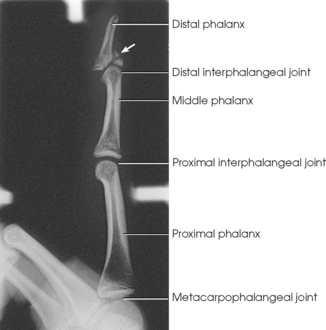

The digits contain 14 phalanges (phalanx, singular), which are long bones that consist of a cylindric body and articular ends. Nine phalanges have two articular ends. The first digit has two phalanges—the proximal and distal. The other digits have three phalanges—the proximal, middle, and distal. The proximal phalanges are the closest to the palm, and the distal phalanges are the farthest from the palm. The distal phalanges are small and flattened, with a roughened rim around their distal anterior end; this gives them a spatulalike appearance. Each phalanx has a head, body, and base.

The interphalangeal (IP) articulations between the phalanges are synovial hinge type and allow only flexion and extension (Fig. 4-8). The IP joints are named by location and are differentiated as either proximal interphalangeal (PIP) or distal interphalangeal (DIP), by the digit number, and by right or left hand (e.g., the PIP articulation of the fourth digit of the left hand) (Fig. 4-9, A and B). Because the first digit has only two phalanges, the joint between the two phalanges is simply called the IP joint.

The metacarpals articulate with the phalanges at their distal ends and the carpals at their proximal ends. The metacarpophalangeal (MCP) articulations are synovial ellipsoidal joints and have the movements of flexion, extension, abduction, adduction, and circumduction. Because of the less convex and wider surface of the MCP joint of the thumb, only limited abduction and adduction are possible.